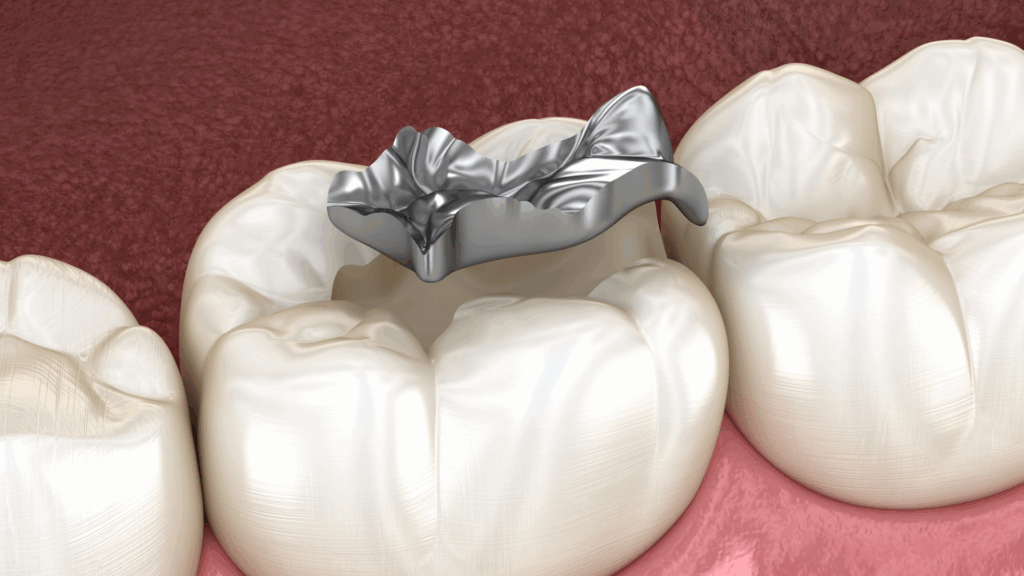

理由2:「隙間」から細菌が侵入する

銀歯(金属)は、歯と化学的に接着するわけではありません。セメント(接着剤)を使って歯に「合着」させているだけです。

このセメントは、お口の中という過酷な環境(温度変化や酸)の中で時間とともに劣化し、溶け出していきます。すると、歯と銀歯の間にわずかな「隙間」が生まれます。

その隙間から細菌が侵入し、銀歯の下、つまり内部でむし歯が再発してしまうのです。これが「二次カリエス」です。銀歯の下は見えないため、患者様ご自身が痛みを感じる頃には、むし歯が神経の近くまで進行しているケースも少なくありません。